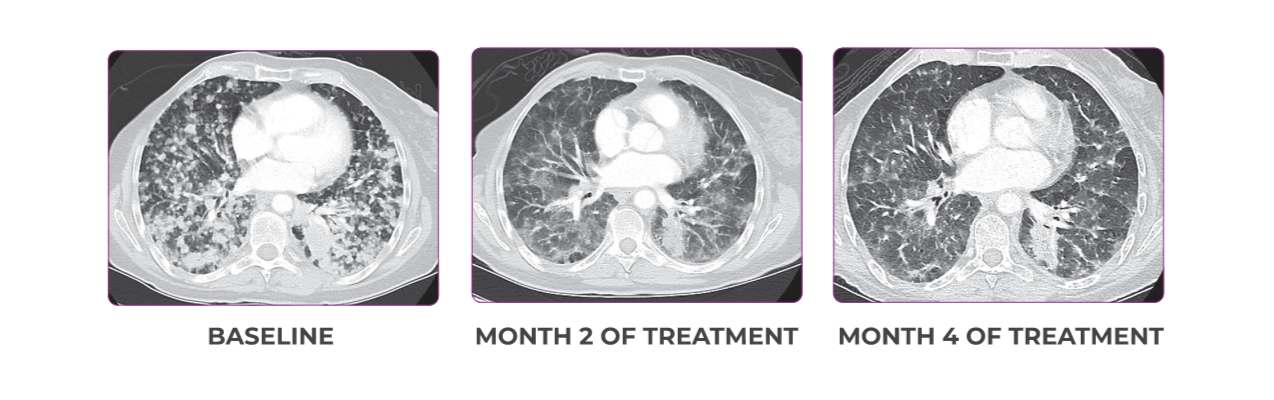

PATIENT CASE:

METASTATIC NSCLC1,a

- PRa after 6 weeks of treatment with VITRAKVI® (larotrectinib)

- Complete clinical response achieved by 12 months with residual scarring

Response to VITRAKVI1

- Partial response and symptom improvement confirmed by chest X-rays after <1 month of treatment

- Imaging performed 6 weeks into treatment revealed considerable decrease in the size of both target lesions

Response in primary and metastatic lesions1

Lung imaging of primary tumors.

SCAN 1: LUNG

SCAN 2: LUNG AND BONE

Images courtesy of Dr Maximilian Hochmair.